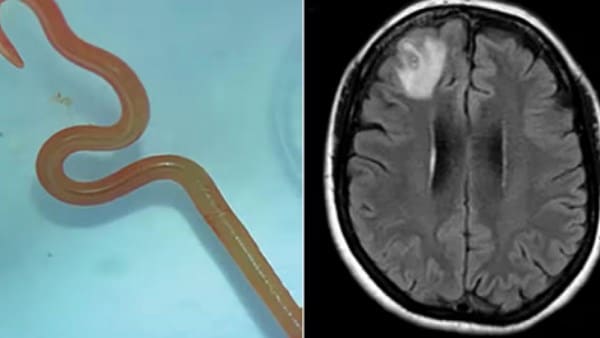

في الشهر الماضي، تفاقمت حالته بشكل حاد، حيث تعرض لنوبات صرع مفاجئة وظهرت رغوة في فمه وفقد وعيه فجأة. بعد فحصه مرة أخرى، اكتشف الأطباء وجود طفيلي حي داخل دماغه. وخلال عملية دقيقة استمرت عدة ساعات، تمكن الجراحون من استخراج دودة بيضاء طويلة، كانت لا تزال تتحرك أثناء إخراجها، ما أثار الدهشة بين الفريق الطبي.

أوضح الأطباء أن العدوى التي أصيب بها المريض تُعرف باسم “داء السبارغانوزيس”، وهو مرض طفيلي نادر ينتقل عبر يرقات الدودة الشريطية الموجودة عادة في الثعابين والضفادع والطيور. ويعتبر تناول اللحوم النيئة أو غير المطهوة جيدًا العامل الرئيسي للإصابة بهذا الطفيل، الذي قد يستقر في الدماغ ويسبب أعراضًا عصبية خطيرة تصل أحيانًا إلى الوفاة.